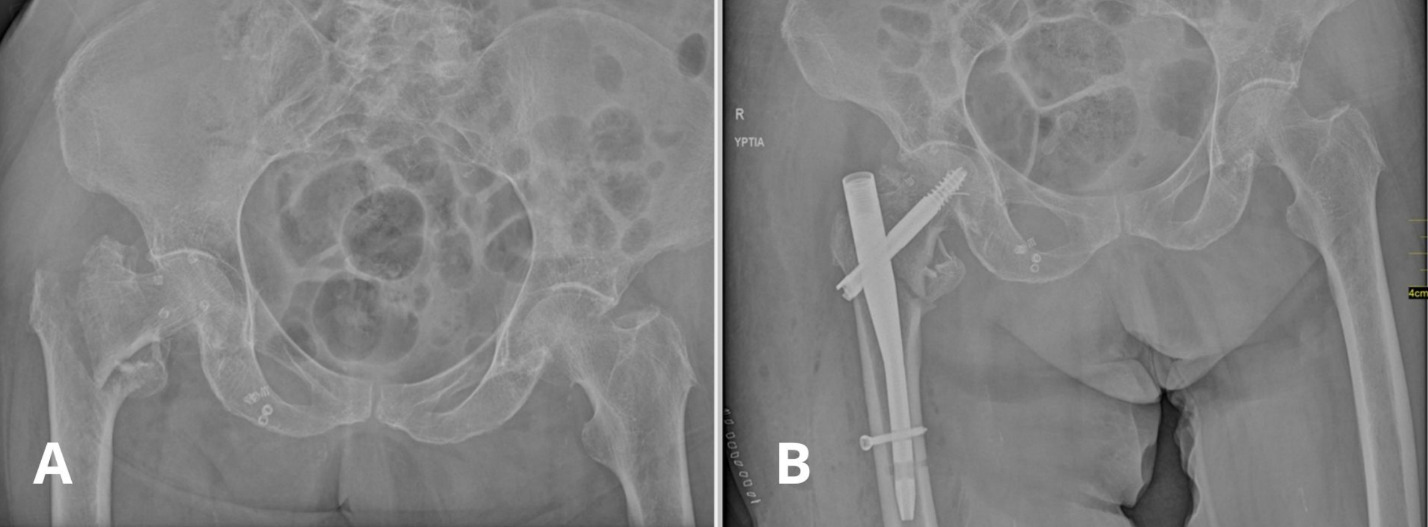

When reviewing the surgical history of the patient, it was revealed that she had sustained a right-sided intertrochanteric (AO/OTA 31A1.3 type) femoral fracture due to fall from her height, one year prior to her current admission. The hip fracture was uneventfully treated with closed reduction and the use of a cephalomedullary intramedullary implant (Dyna Locking Trochanteric DLT™ Nail, U & I Corporation 529-1,Yonghyun-dong, Uijungbu Kyunggi-Do, Korea). Figure 2 shows the preoperative radiographic image of the fracture and the immediate postoperative X-Ray. There were no postoperative complications and the patient was discharged at a rehabilitation center with instructions to bear weight as tolerated. According to her caregiver the patient was doing well and walking with minimal support, and therefore she did not visit our outpatient clinic for regular follow-up.

_anteroposterior_radiograph_of_the_pelvis_showing_a_displaced_intertrochanteric_fractur.png)